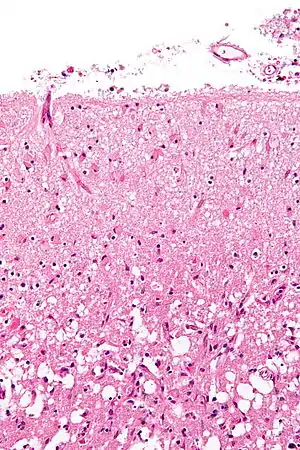

Hemorrhagic

Hemorrhagic strokes are classified based on their underlying pathology. Some causes of hemorrhagic stroke are hypertensive hemorrhage, ruptured aneurysm, ruptured AV fistula, transformation of prior ischemic infarction, and drug-induced bleeding.[60] They result in tissue injury by causing compression of tissue from an expanding hematoma or hematomas. In addition, the pressure may lead to a loss of blood supply to affected tissue with resulting infarction, and the blood released by brain hemorrhage appears to have direct toxic effects on brain tissue and vasculature.[43][61] Inflammation contributes to the secondary brain injury after hemorrhage.[61]